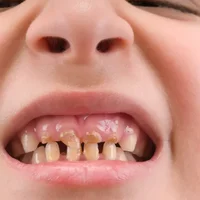

Caries dentaires graves

Bouche et dents

Caries dentaires chez les enfants